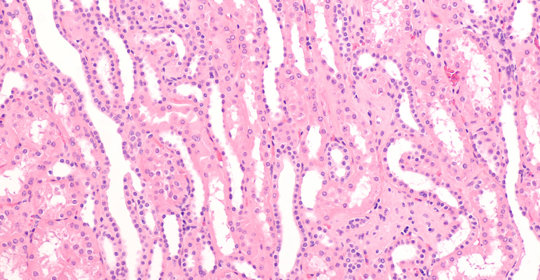

乳房囊腫:病因、診斷與治療

乳房囊腫:分類與處理

乳房腫塊:症狀、原因及診斷